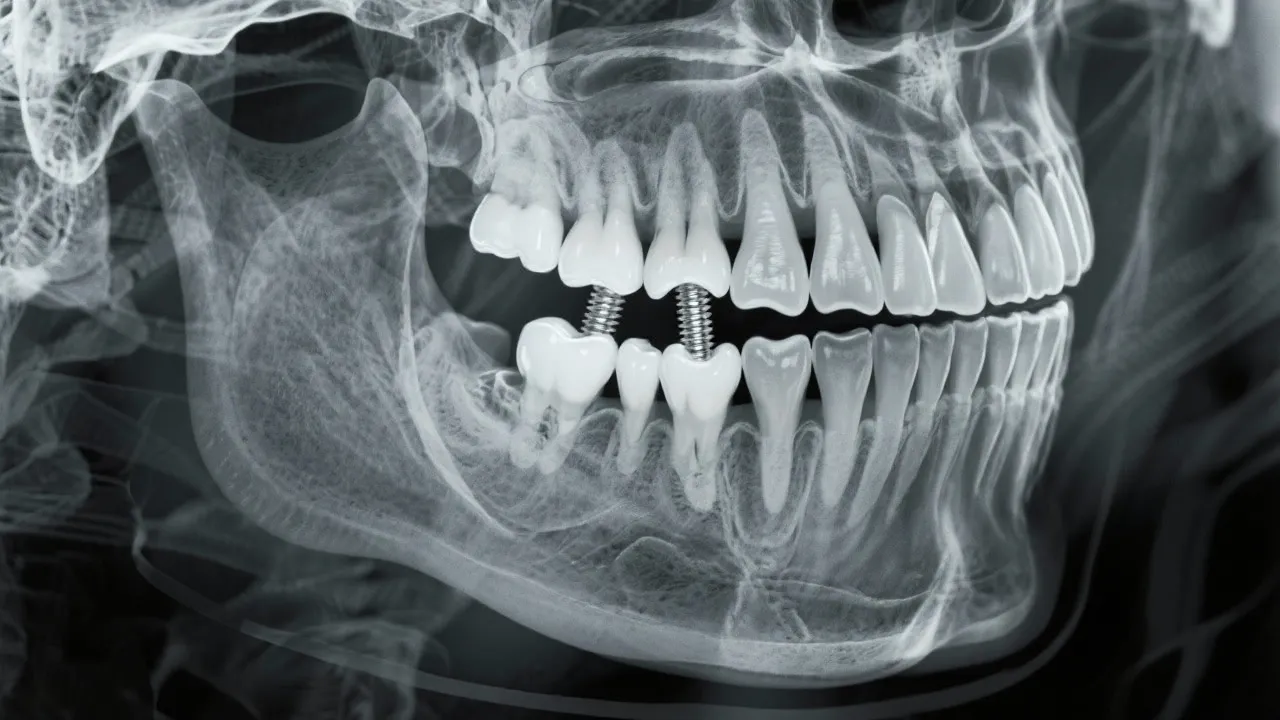

This thorough guide explores the crucial relationship between bone density and dental implants. Bone density plays an integral role in implant success, determining the stability and integration of the implant into the jawbone. Understanding this connection aids in making informed decisions regarding dental health.

Bone density is a critical factor when considering dental implants. It refers to the amount of bone material present in a specific volume of bone, which directly impacts an implant's stability and longevity. Adequate bone density ensures that the dental implant can support the forces of chewing and other oral functions. Inadequate bone density, however, may lead to complications, affecting the implant's success rate. High bone density provides a stronger anchorage point, which is essential for the integration of the implant within the jawbone. When evaluating candidates for dental implants, dentists often conduct imaging studies like X-rays or CT scans to assessbone density patterns and bone structure.

Impact of Bone Density on Implant Success

Successful dental implantation requires not only the technical skill of the dental surgeon but also the biological readiness of the patient’s jawbone. High bone density provides a solid foundation for implants, reducing the likelihood of structural failure. Despite the importance of bone density, many patients may be deterred by recommendations for additional procedures like grafting. Understanding how these interventions can lead to better long-term results is essential for informed decision-making.

In cases where bone density is questionable, preemptive measures such as bone grafting or the use of mini implants may be considered. Mini implants, which are narrower in design, can sometimes be placed without extensive grafting procedures; however, they may not be suitable for all patients or types of restorations. Collaborating closely with your dental team can help to devise the best approach tailored to your specific situation.